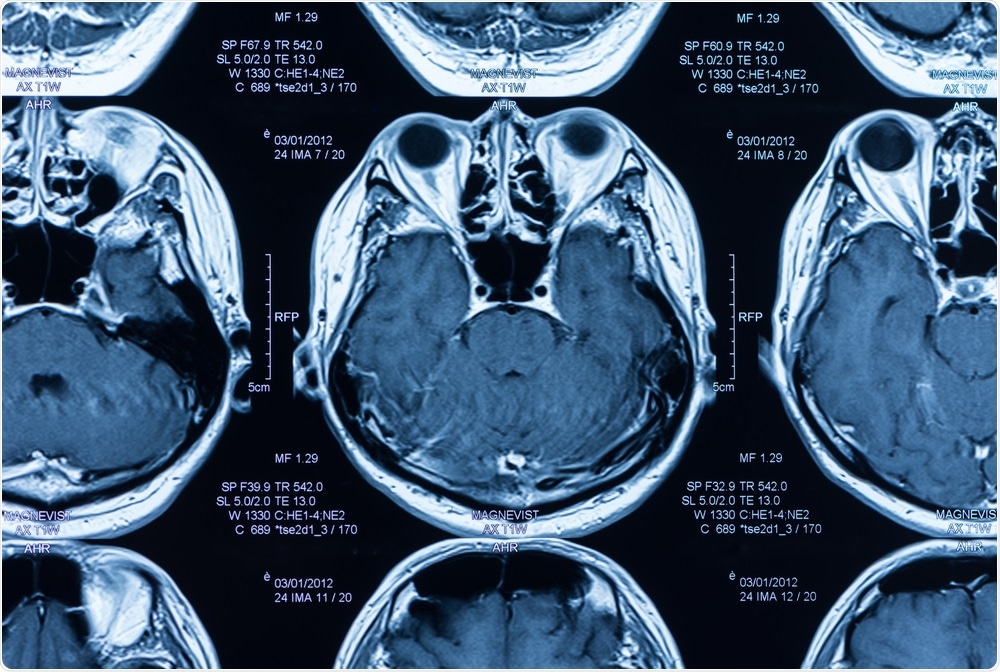

The research team analyzed magnetic resonance imaging (MRI) scans and found that higher levels of body fat were associated with reduced volumes of gray matter and an increased likelihood of changes in the white matter.

For the current study, Dekkers and team analyzed MRI scans available for 12,087 participants (aged an average of 62 years) from the UK Biobank study and assessed the gray- and white-matter structure of their brains. They also measured the participant's levels of body fat using a method called bioelectrical impedance, which provides an estimate of body fat percentage.